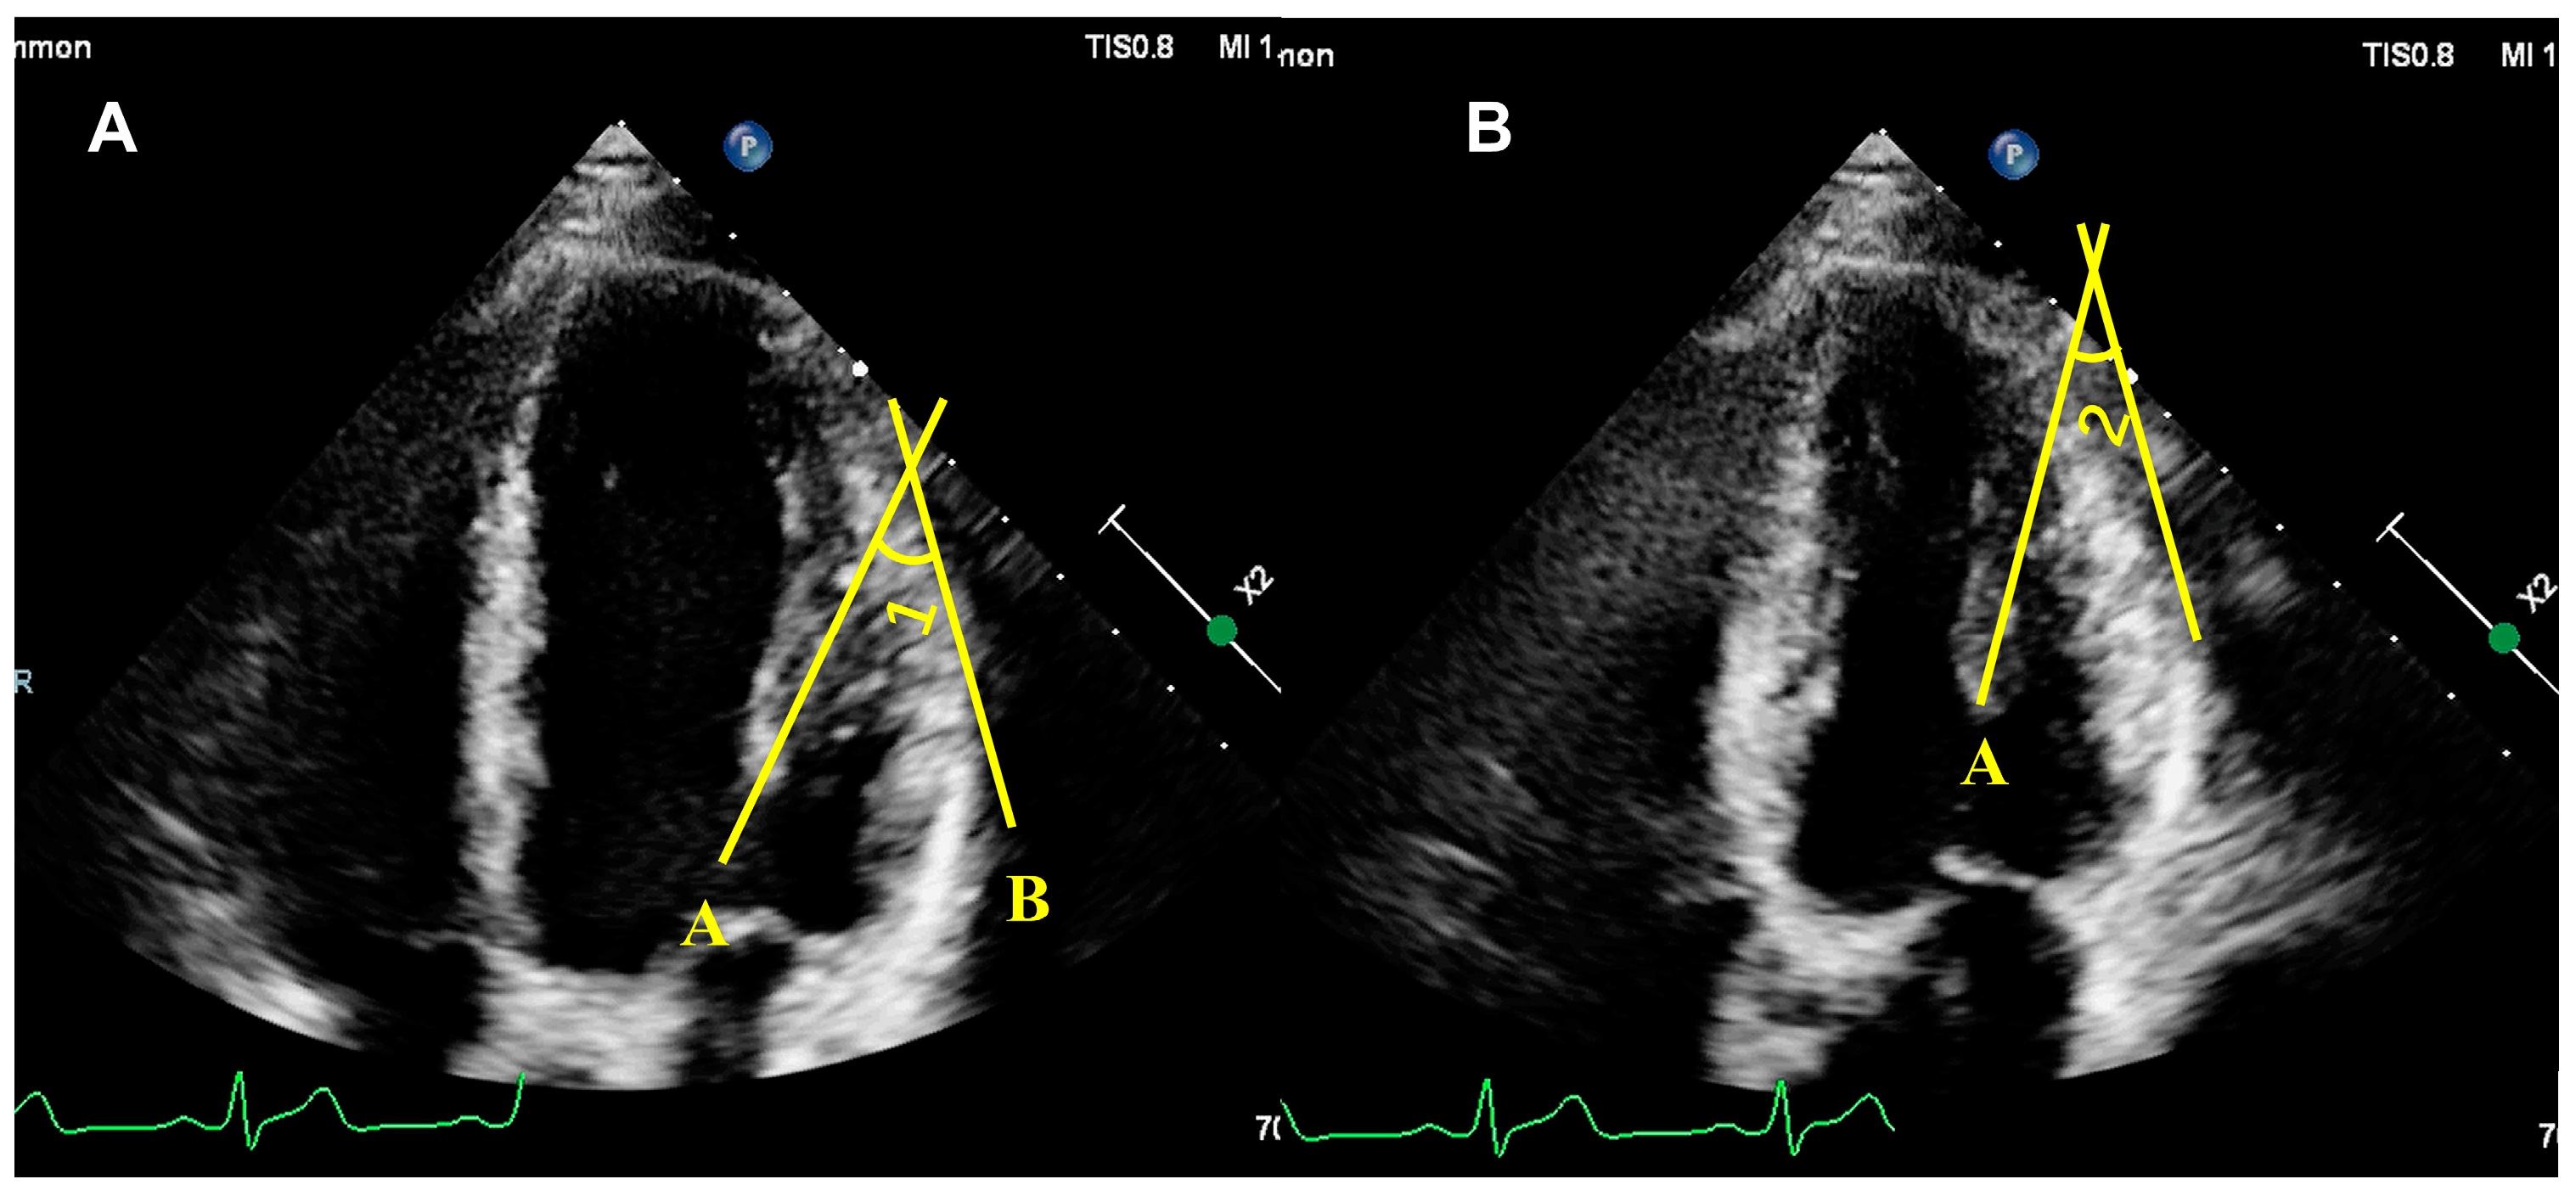

5.2.2. Quantitative Assessment of PM Function